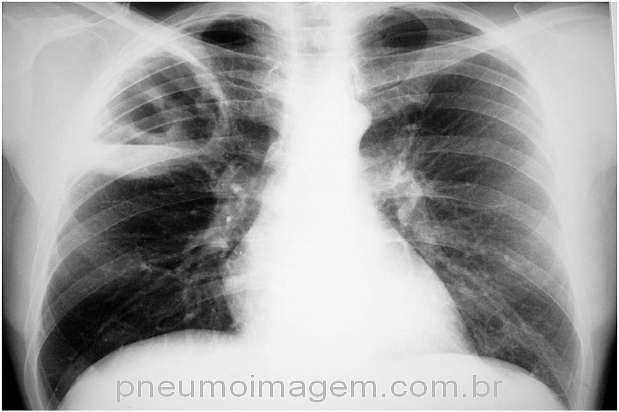

CASO CLÍNICO #37

Paciente se apresenta com febre e expectoração abundante. Qual o diagnóstico mais provável? Deixe os seus comentários abaixo.

Patient presents with fever and abundant expectoration. What is the most likely diagnosis? Give your comments below.